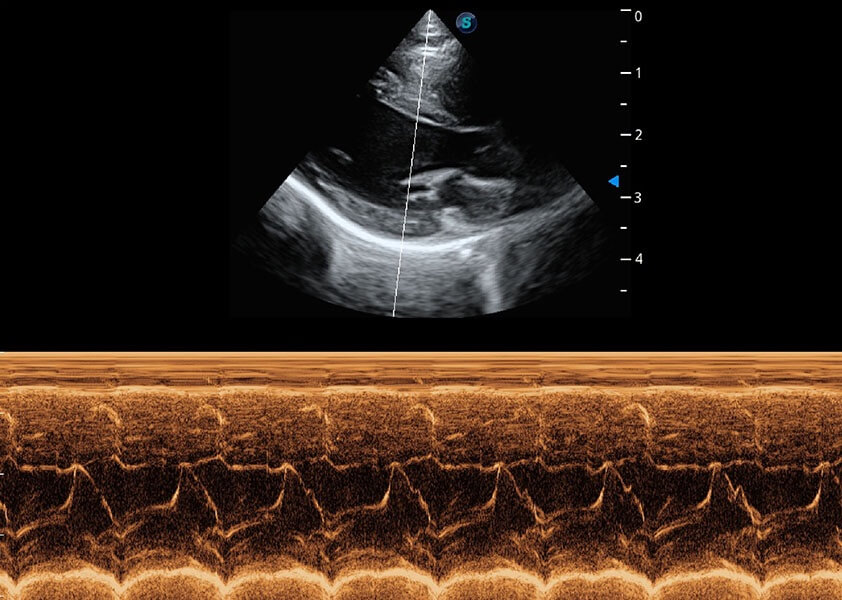

ProPet 60 作为一款高端台式动物超声设备,为动物医生的日常诊断提供了一系列贴合动物临床需求、解决临床实际问题的高级成像功能。凭借全系列高清探头,满足医生对腹部、心脏、生殖、浅表、肌骨等成像的所有需求,切实帮助您提升检查效率,提高诊断信心。

动物是人类最亲密的朋友和最值得信赖的伙伴。乐玩lewin国际也一直致力于探索动物专用的超声影像解决方案。 全新推出的ProPet系列,是乐玩lewin国际在动物超声影像智能化、专业化、精准化的一次跨越式革新。动物不能用言语来表述自己的不适,通过超声影像,ProPet系列搭建了动物医生与不同物种沟通的“桥梁”,为动物医生注入了“治愈之力”。